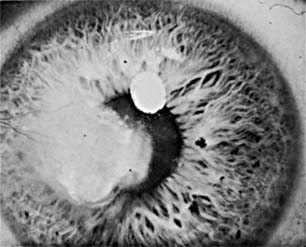

Fungal ulcers are indolent and have a gray infiltrate, often a hypopyon, marked inflammation of the globe, superficial ulceration, and satellite lesions (usually infiltrates at sites distant from the main area of ulceration) (Figure 6-3). The principal lesion-and often the satellite lesions as well-is an endothelial plaque with irregular edges underlying the principal corneal lesions, associated with a severe anterior chamber reaction and a corneal abscess.

Figure 6-3

Figure 6-3: Corneal ulcer caused by Candida albicans.

Most fungal ulcers are caused by opportunists such as Candida, Fusarium, Aspergillus, Penicillium, Cephalosporium, and others. There are no identifying features that help to differentiate one type of fungal ulcer from another.